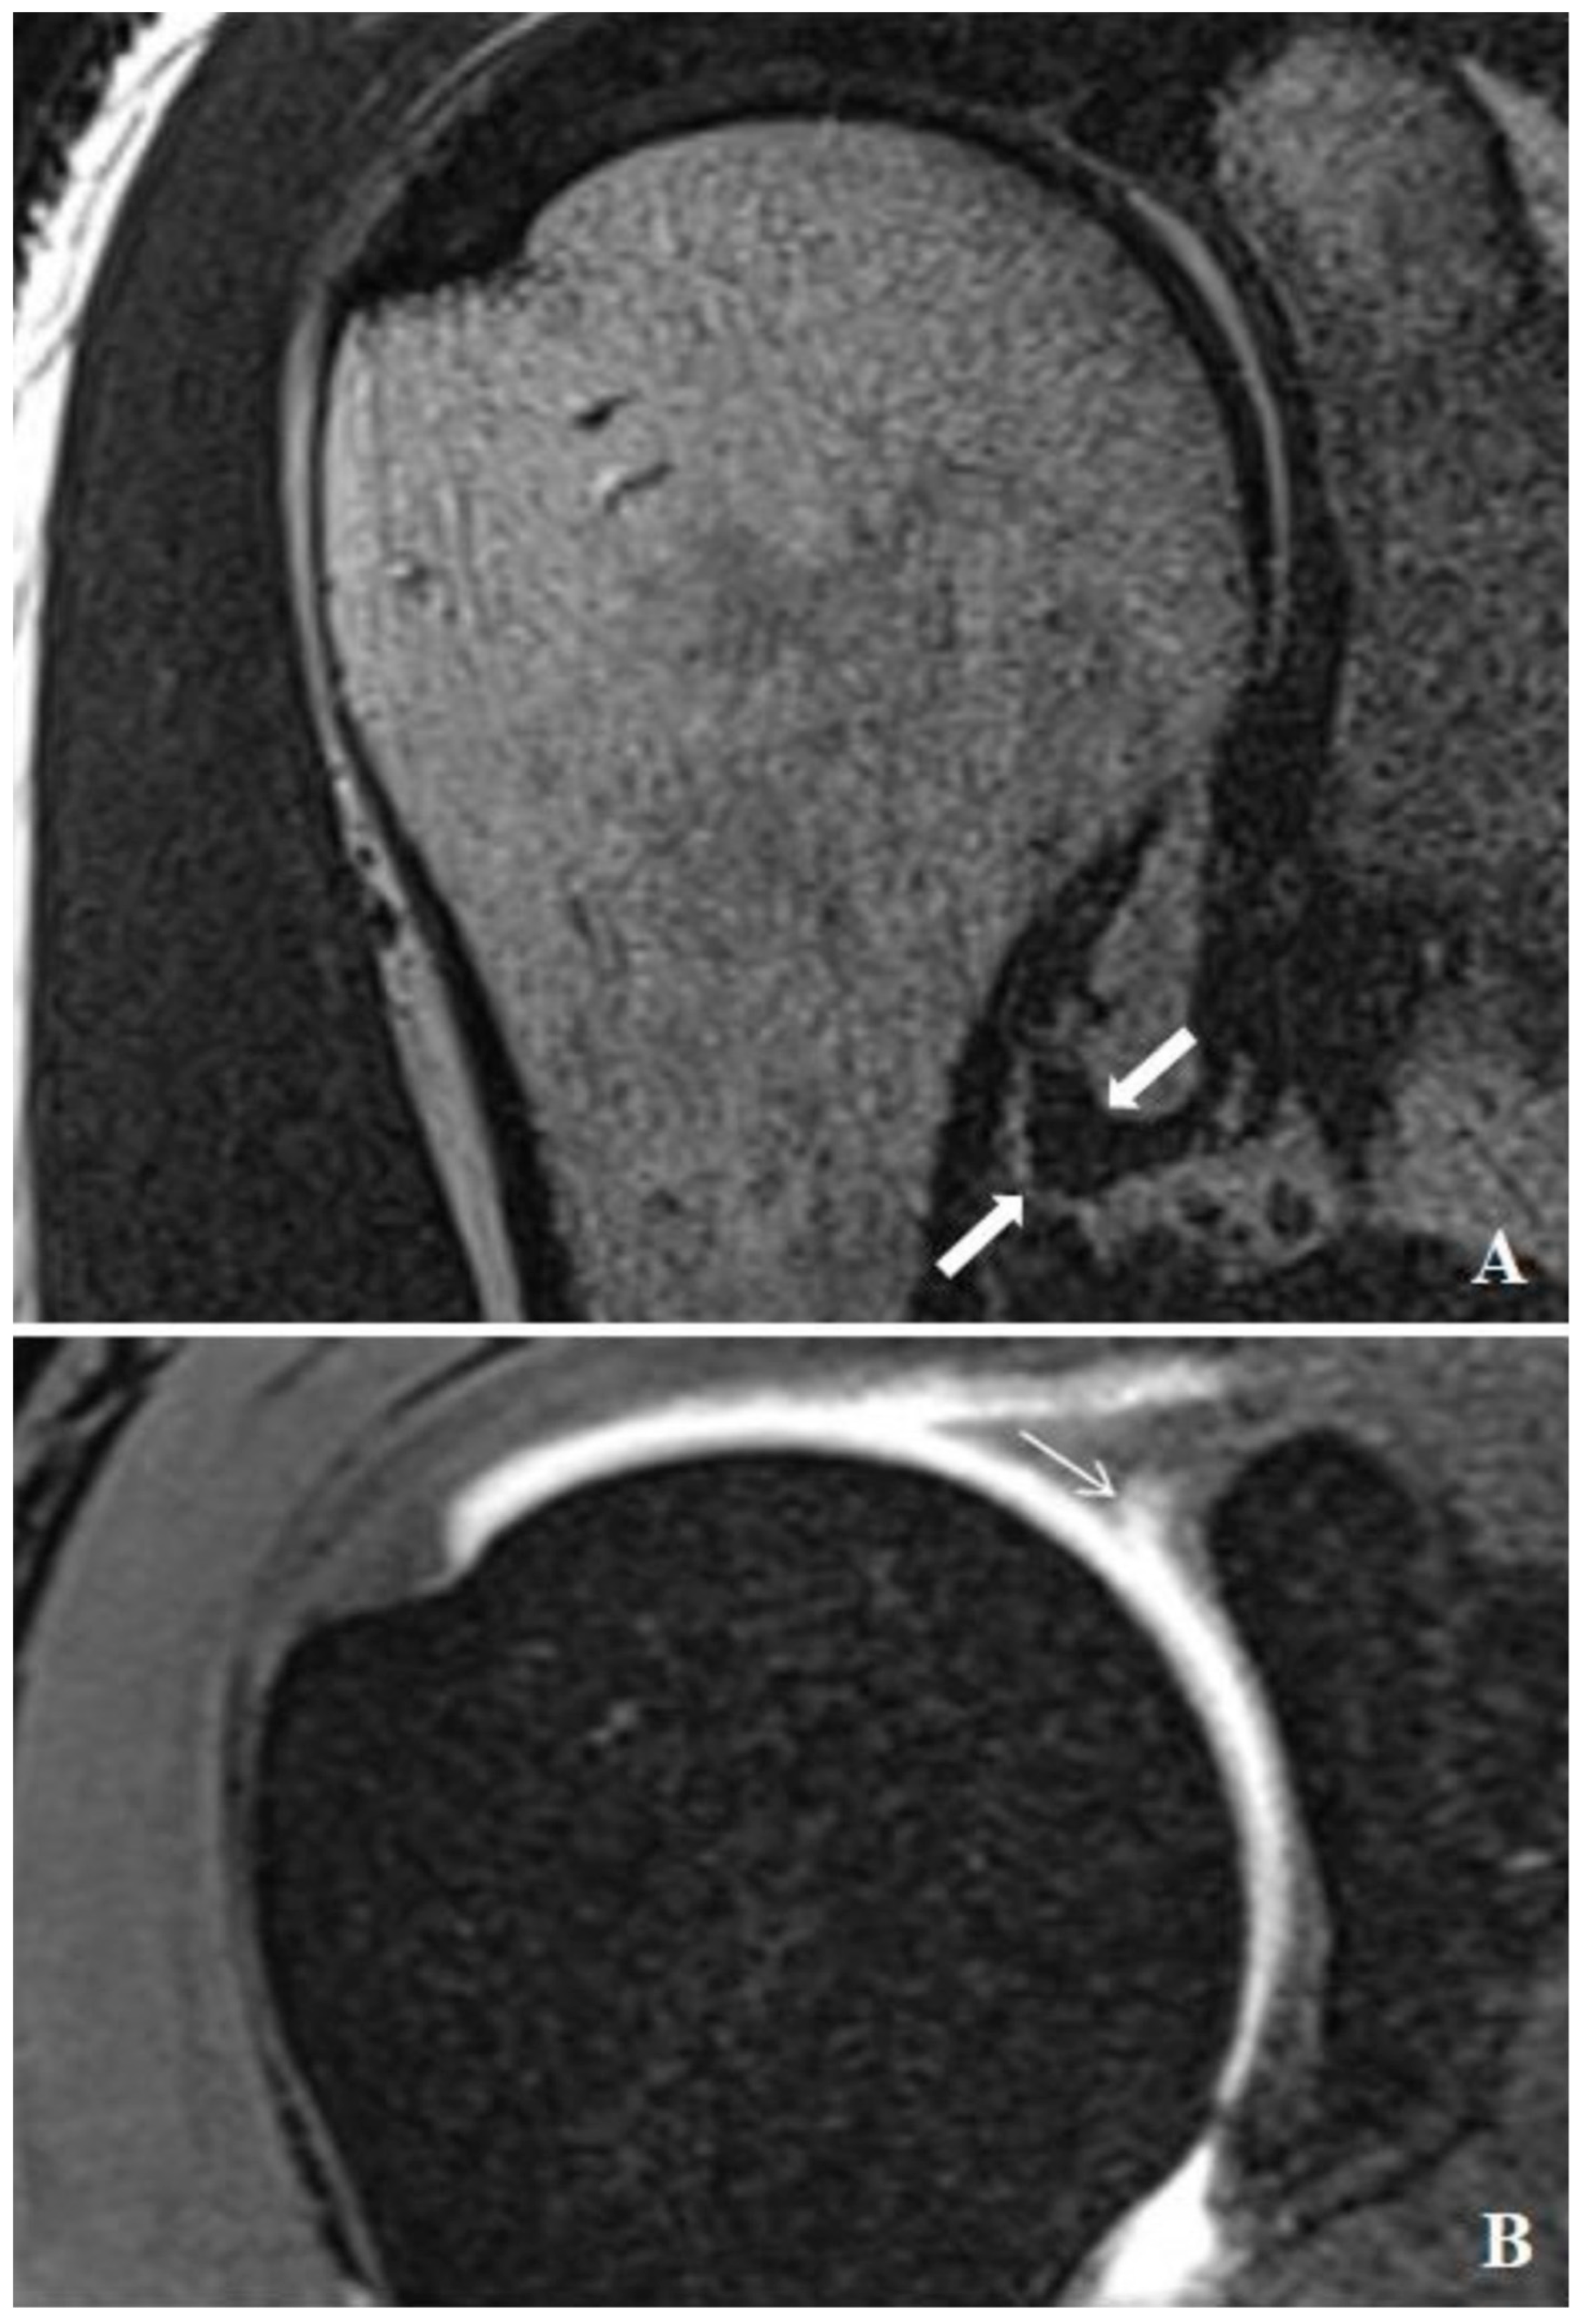

Relationship between SLAP Lesions and Shoulder Joint Capsule Thickness: An MR Arthrographic Study

Güçlü, D.; Uludağ, V.; Arıcan, M.; Ünlü, E.N.; Oğul, H. Relationship between SLAP Lesions and Shoulder Joint Capsule Thickness: An MR Arthrographic Study. Medicina 2024, 60, 1332. https://doi.org/10.3390/medicina60081332